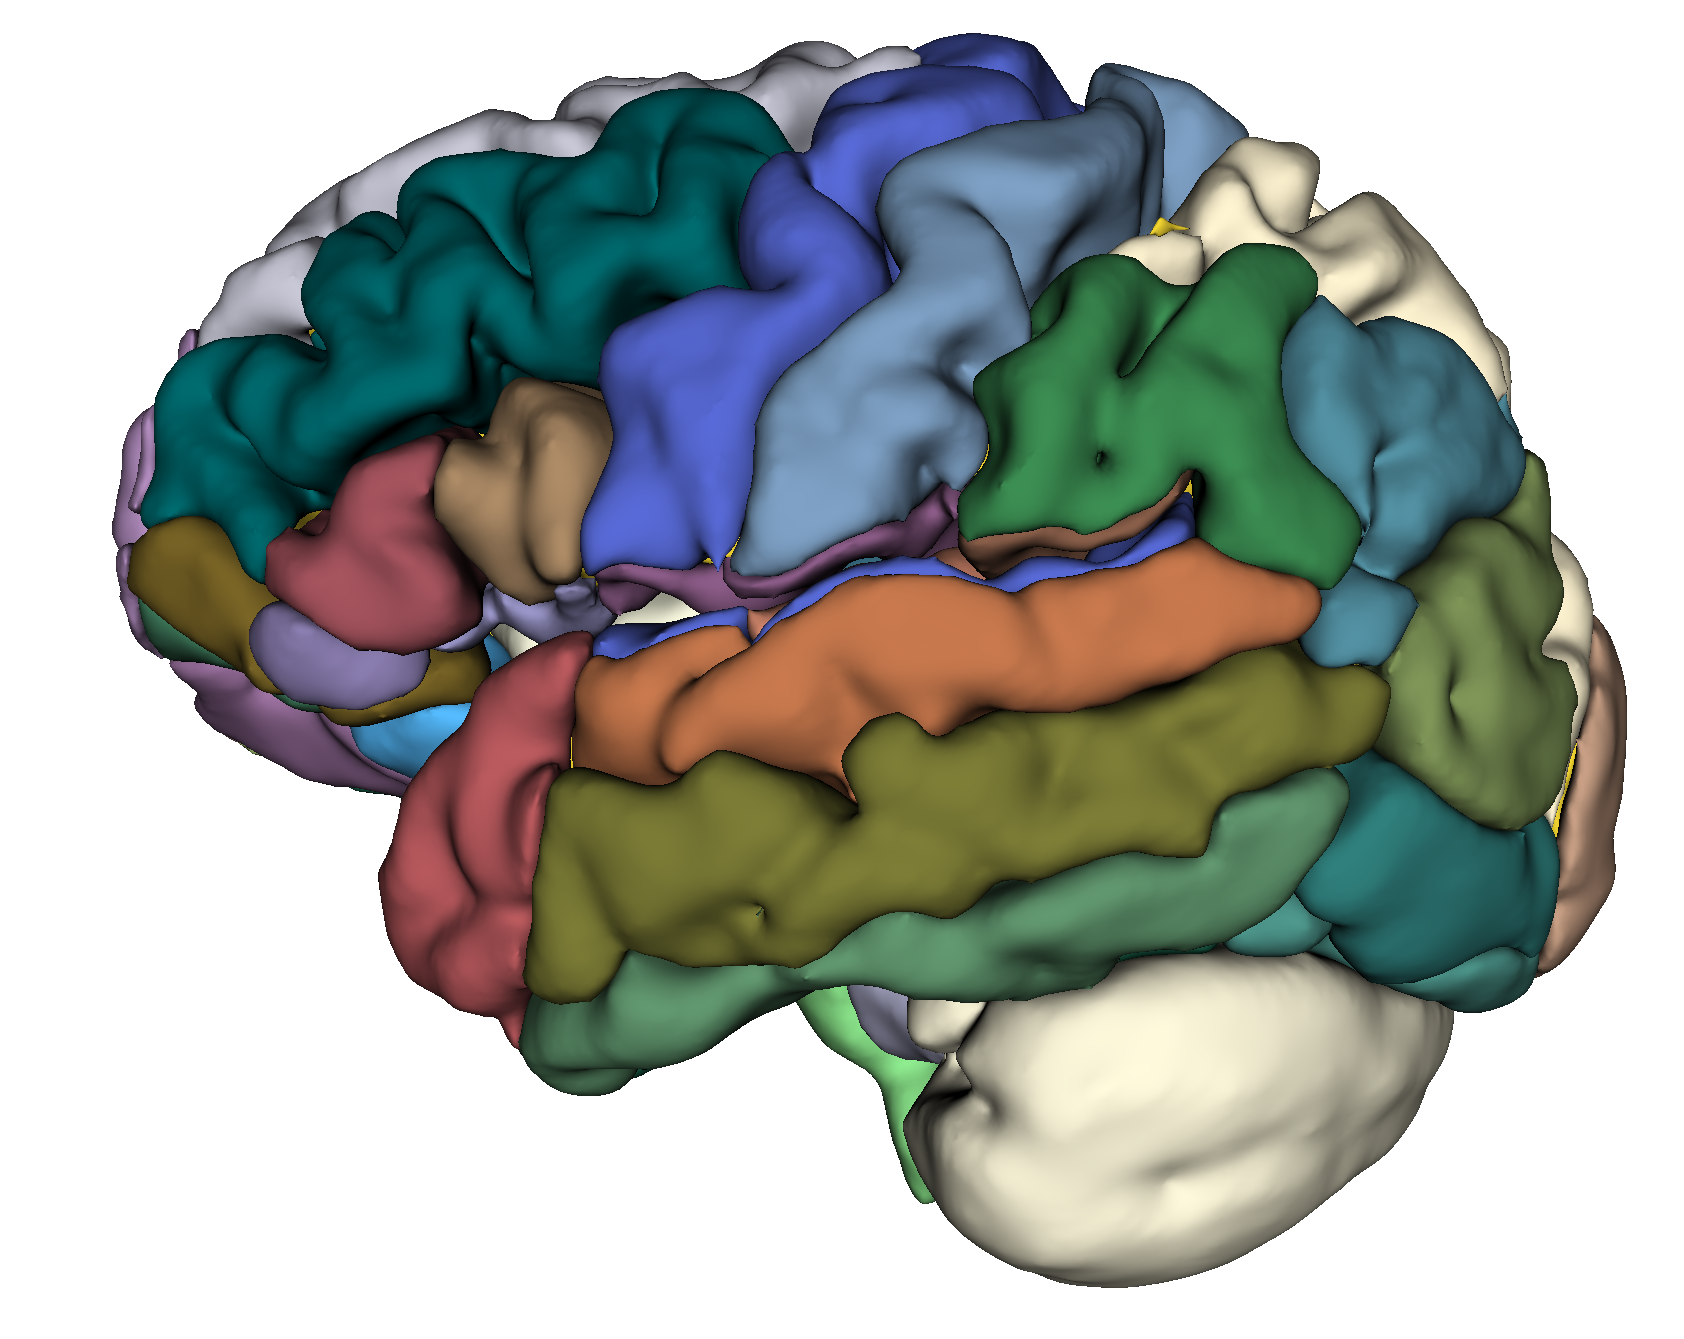

Die anhaltende Minderdurchblutung des Gehirns bei Moyamoya Patientinnen und Patienten kann das Gehirn nicht nur durch manifeste Schlaganfälle schädigen, sondern auch durch die chronische Unterversorgung. Dies kann über die Jahre zu einem Verlust von Hirnvolumen (Hirnatrophie) führen. In einer großen Studie haben wir die Hirnvolumina von Moyamoya Patientinnen und Patienten mit denen von gesunden Probanden verglichen. Hierbei konnten wir zeigen, dass Patienten dieser Studie ohne im MRT sichtbare Schlaganfälle eine Altersverschiebung der Hirnatrophie von rund 45 hin zu 58 Jahren hatten. Das heißt in anderen Worten, dass die chronische Minderversorgung des Gehirns dieser Patientinnen und Patienten diese um 13 Jahre über den Altersdurchschnitt hat altern lassen.

Grafik Gehirn mit Arealen in Farben

Exemplarische Darstellung eines komplett segmentierten Gehirns zur Berechnung der jeweiligen Hirnvolumina.